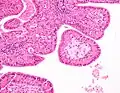

Low magnification micrograph of a Warthin tumor arising from the parotid gland.

Histopathology of Warthin tumor in the parotid gland. H&E stain.